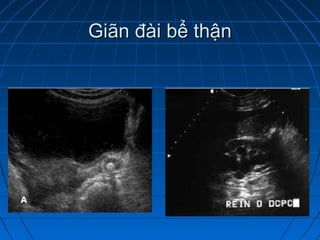

 Giãn đài bể thậnGiãn đài bể thận

Giãn đài bể thậnGiãn đài bể thận